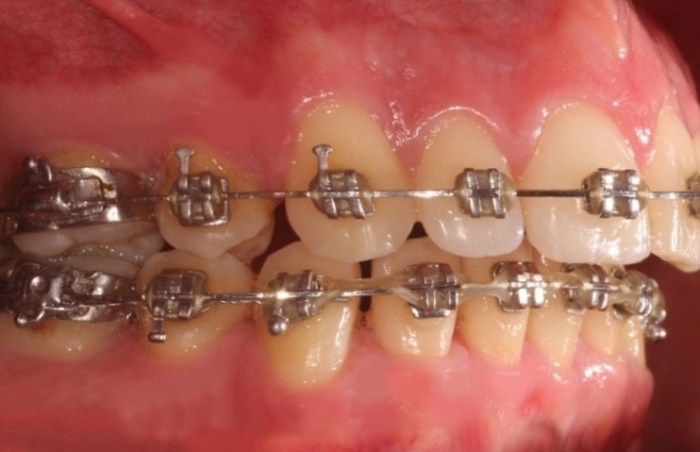

Mordida inicial